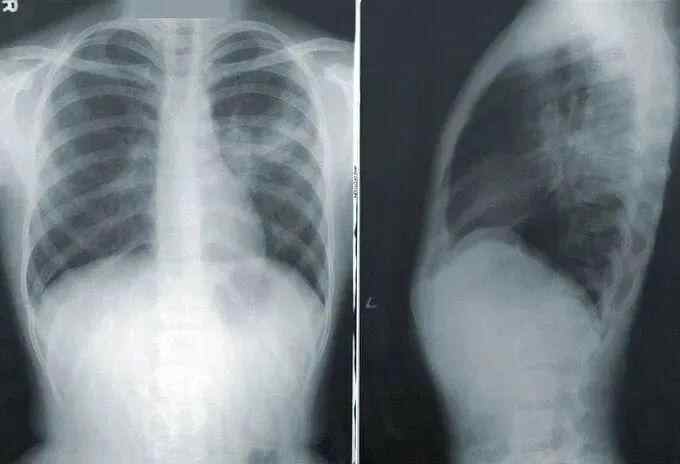

杭州市一医院胸外科副主任医师胡润磊曾接诊过一对张姓肺癌患者。

据悉,二人为夫妻关系,且在体检时同时查出肺结节。后经胡润磊的进一步诊察,最终确诊夫妻二人同患早期肺癌!